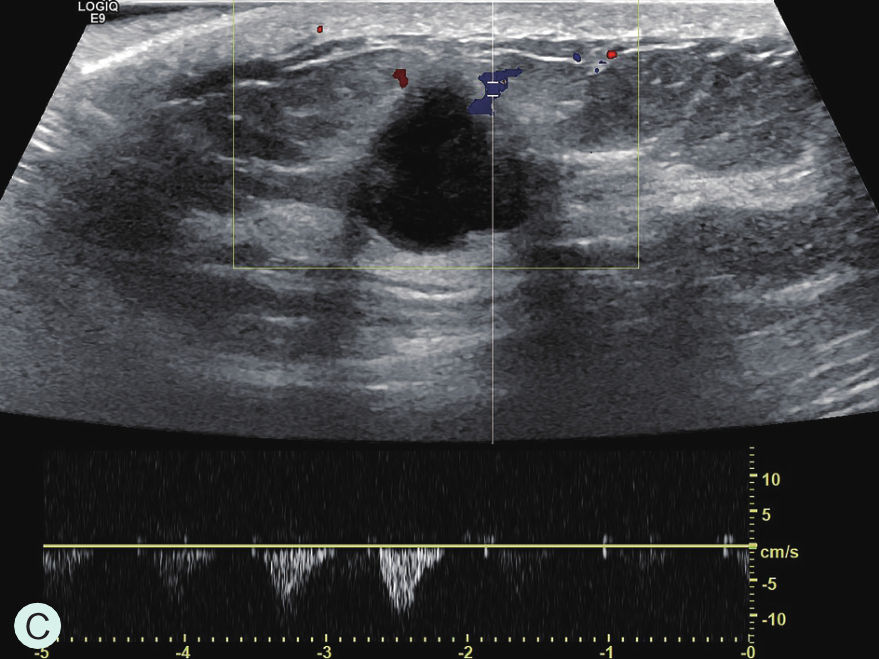

图2-2-8 分析与判读

A.同步测量病灶大小与高增强范围;B.勾勒病灶与增强范围;C.定量分析